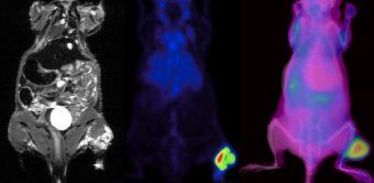

Probevortrag Ronald J. H. Borra, MD, PhD (Multimodale Bildgebung und nuklearmedizinische Therapie)

Probevortrag Ronald J. H. Borra, MD, PhD (Multimodale Bildgebung und nuklearmedizinische Therapie)